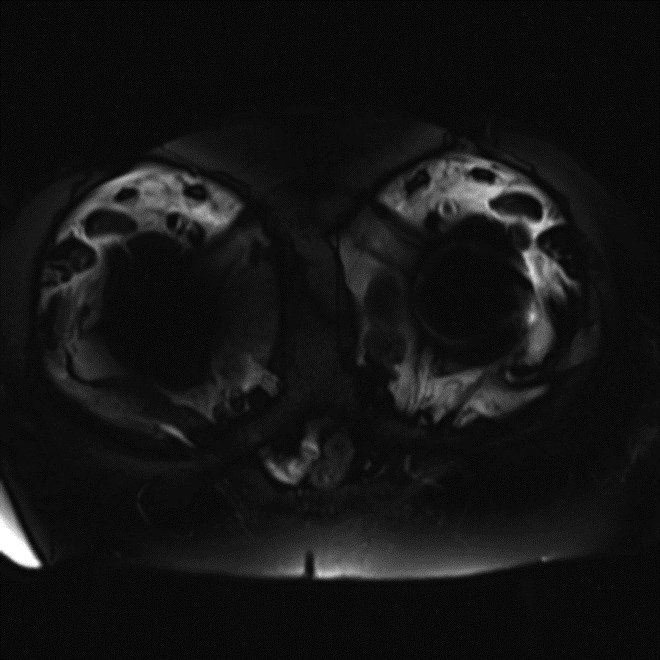

Inversion Recovery Imaging. (A) Axial spectral adiabatic inversion recovery (SPAIR) image used during MR examination of the abdomen and pelvis demonstrates large regions of susceptibility due to bilateral metal-on-metal hip arthroplasties as this technique is highly sensitive to field inhomogeneities.

| Inversion Recovery Imaging. (B) Axial STIR MR image in the same patient reveals fluid-signal pseudotumor (arrow) adjacent to the left greater trochanter, which was obscured on prior examination. |